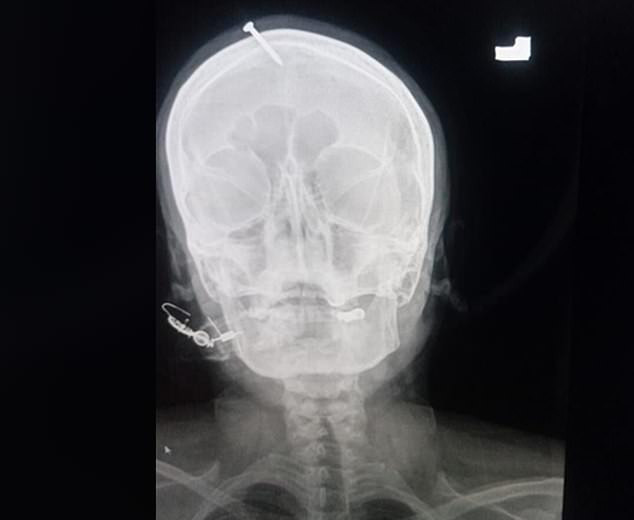

An X-ray showed the two-inch nail had pierced the top of the woman’s forehead but missed her brain.